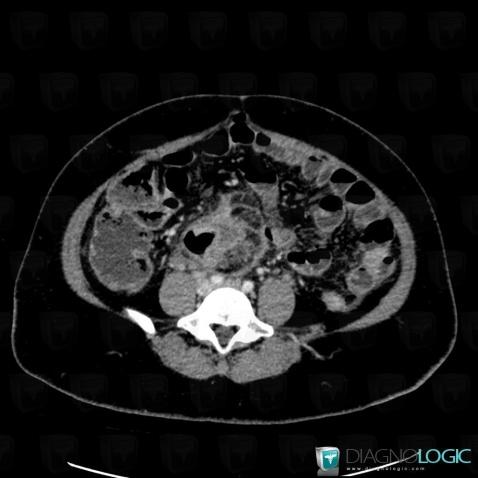

Pneumoperitoneum, Mesentery / Peritoneum, CT

Here is the specific information in the key image above:

- Diagnosis Pneumoperitoneum, Location(s) Mesentery / Peritoneum, with gamuts

Colon cancer, Colon, CT

- Diagnosis Colon cancer, Location(s) Colon, with gamuts Thickening of colon wall, Colonic mass or filling defect

Abscess, Retroperitoneum, CT

- Diagnosis Abscess, Location(s) Retroperitoneum, with gamuts